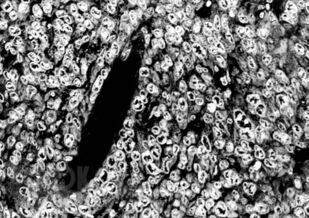

Книга посвящена описанию животных моделей in vivo для отбора, углубленного и/или доклинического изучения цитостатиков, а также некоторых таргетных средств. Представлены основные биологические характеристики, дополненные лекарственной чувствительностью и востребованностью в настоящее время.